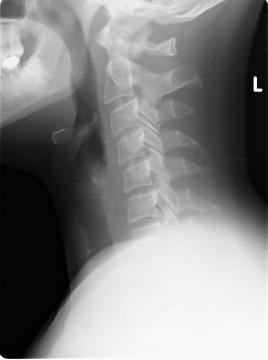

Pro větší náhled klikněte na obrázek

Dobrý den,před měsícem jsem prodělal polohové vertigo při obracení v posteli na levý bok, vertigo trvalo cca 1-2 min. a bylo provázeno pocitem na zvracení a trošku zvracením a rozmazaným viděním, druhý den se mi stalo totéž (bez zvracení) při otočení na levý a po chvíli znovu i na pravý bok. Byla mi provedena různá vyšetření na ORL a neurologii (CT, lumbální punkce, EEG, evokované potenciály VEP a BAEP, polohové testy a nic nemylo nalezeno). Ve výsledcích vyšetření mám nystagmus=0, testy na BPPV negativní). Byl jsem propuštěn s tím, že jde o suspektní polohové vertigo a budu několik týdnů užívat lék Betaserc. Na neurologii mi bylo řečeno, že to je vše a že jsem neurologicky i objektivně zdravý. Závrať se již nevrátila, nicméně od té doby se mi několikrát denně stane, že mám při čtení nebo např. koukání na televizi pocit, že mi trošku škubnou/mírně ujedou oči doleva a při tom mnou projede teplo do žaludku (něco jako leknutí) a někdy mi při tom bouchne silně srdce. Nejsem si jist, zda se tak děje najednou nebo je nejdřív pohyb očí a až potom projetí tepla a bouchnutí. Určitě bych měl také uvést, že jsem před třemi roky měl problémy s úzkostmi a beru lék elicea. Od chvíle, co ho užívám jsem ale žádné problémy nepociťoval a normálně funguji. Vím, že neznáte konkrétní případ, ale zajímal by mne spíše Váš názor: 1) může být příčinou pocitů v očích (a případně i vertiga) páteř? (dle rtg mám plně vyhlazenou krční a bederní lordózu a počínající změny na obratlích c2 a c3 viz přiložený rtg), 2) může být příčinou pocitů v očích psychika a stres? (od chvíle hospitalizace jsem neustále ve strachu, že může jít o nádor na mozku, protože příliš nevěřím, že jsem zdraví, když mám ony pocity v očích). Děkuji předem za Váš čas a případnou odpověď.Petr